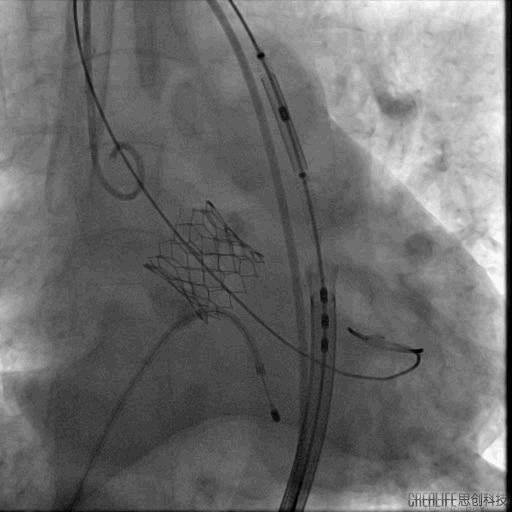

然而瓣膜释放后患者出现室颤,再次面临命悬一线的险境,术者团队处危不惊,快速予以除颤处理,患者成功恢复为窦性心律,转危为安。

复查造影示轻度主动脉瓣返流,同时行床边经食道心脏彩超,未见明显瓣周漏,瓣膜功能良好。升主动脉压力156/92mmHg,跨瓣压差<10mmHg。患者生命体征平稳,送返病房,密切监测生命体征变化。

最后造影